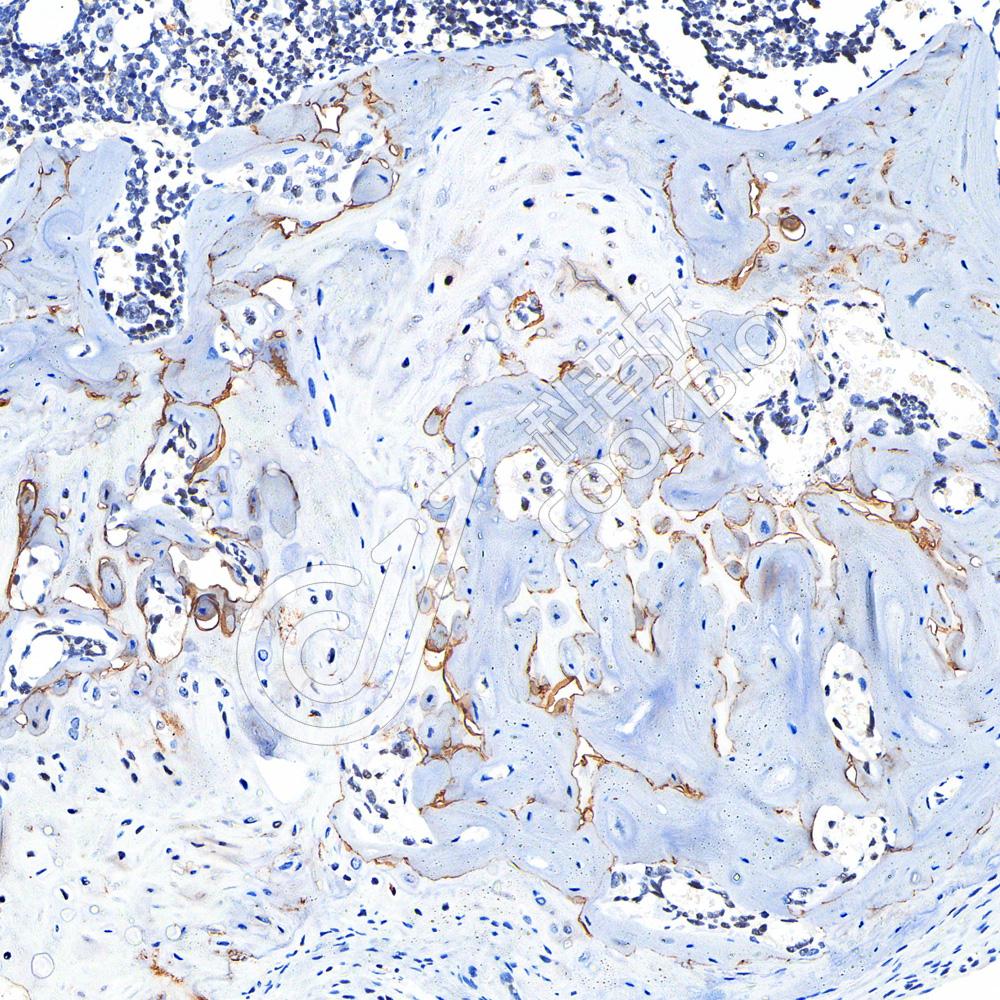

IHC检测ErbB2/HER2蛋白(货号 K1341913).

样品: 人乳腺癌, 4%多聚甲醛 (货号KSG1101) 固定12-24小时.

抗原修复: 柠檬酸抗原修复液(干粉, pH 6.0) (KSG1201), 98℃, 20分钟.

—抗: 1: 800稀释, 4℃ 孵育过夜.

二抗: S-vision免疫组化多聚二抗(山羊抗兔),即用型 (货号KB3906), 室温孵育20分钟.